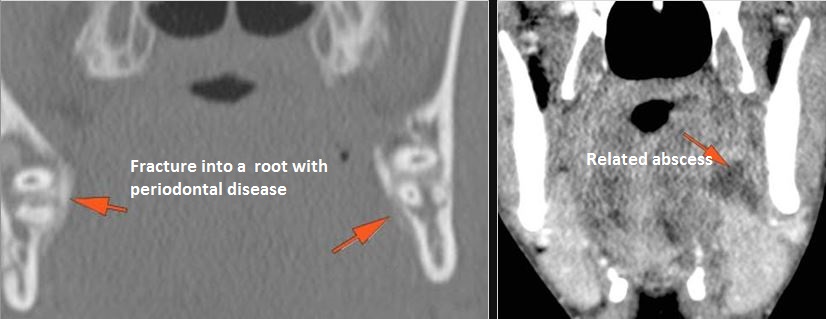

Dentition

There are dental fractures and/or missing or displaced teeth.

Facial and Scalp Soft Tissues and Airway

There is localized edema, hematoma or abscess within in the facial or scalp soft tissues, SMAS, infratemporal fossa, masticator space or oral cavity.